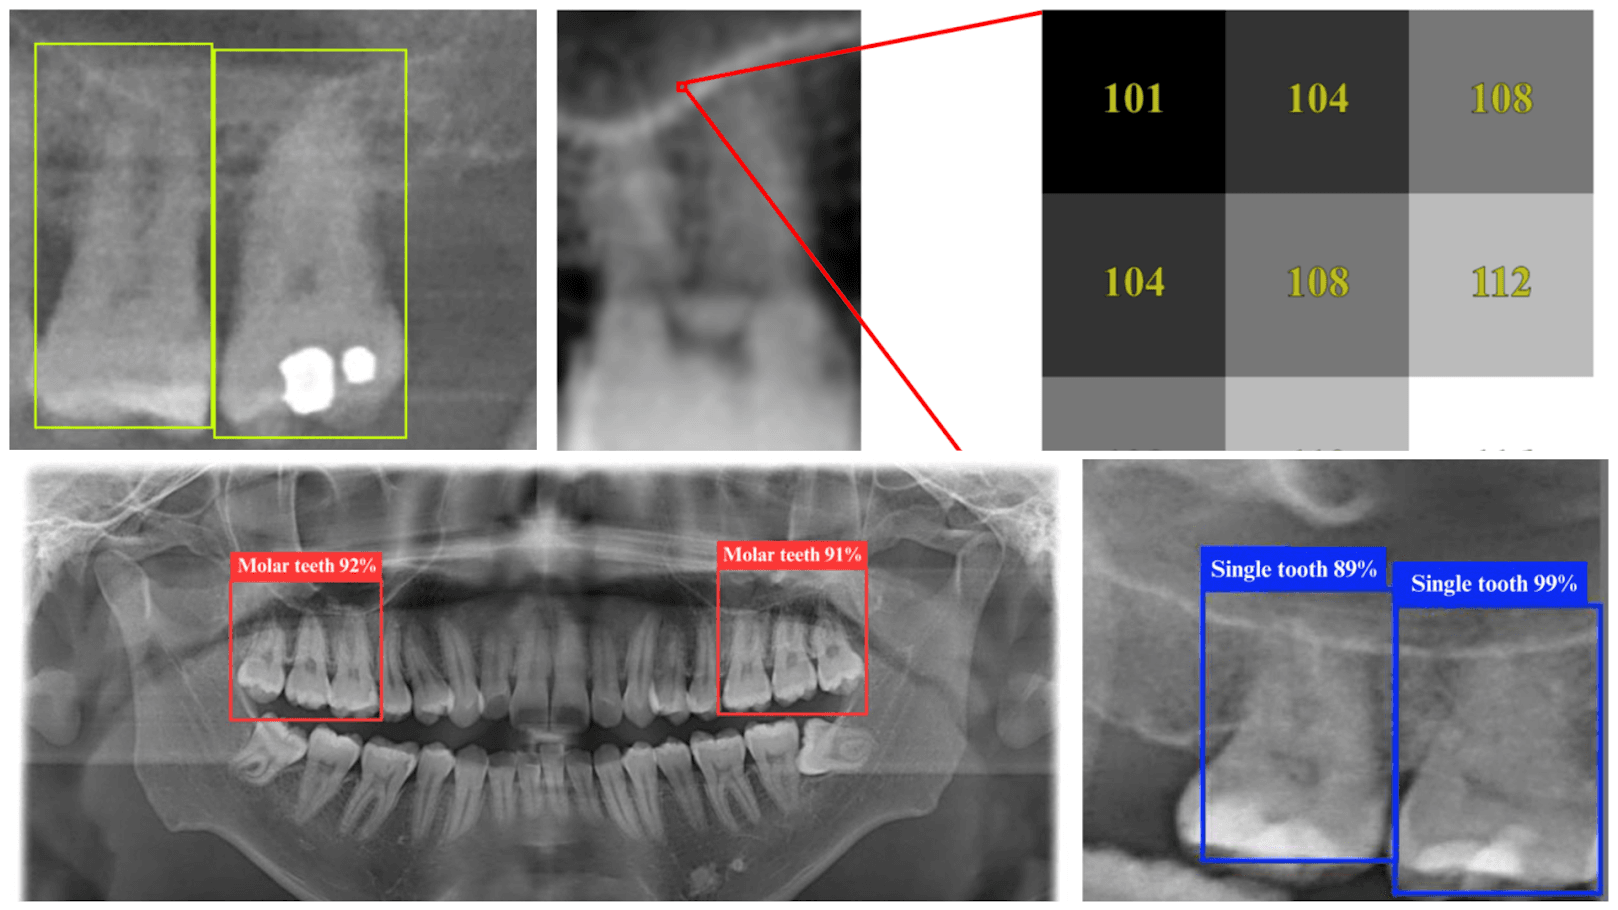

Sample dental X-rays or dental panoramic radiographs (DPRs) as seen by the YOLO 11n deep learning model, which is able to identify tooth structures with up to 98.2% accuracy. (Credit: Pei-Yi Wu et al., 2025) Artificial Intelligence (AI) has gained a notorious reputation in specific fields...